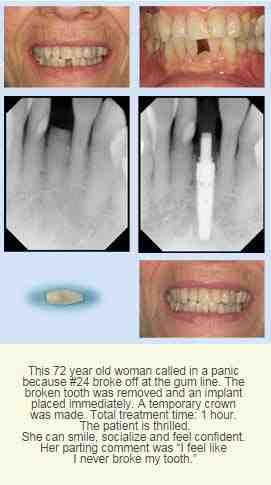

Can you get Implant same day as extraction?

Same-day Dental Implants provide quick results but osseointegration must be done for the operation to be successful in the long run. Staying together in the chin will take a long time. During the procedure, final patients are strongly advised to repeat the guidelines.

Can you get a temporary tooth while waiting for an implant?